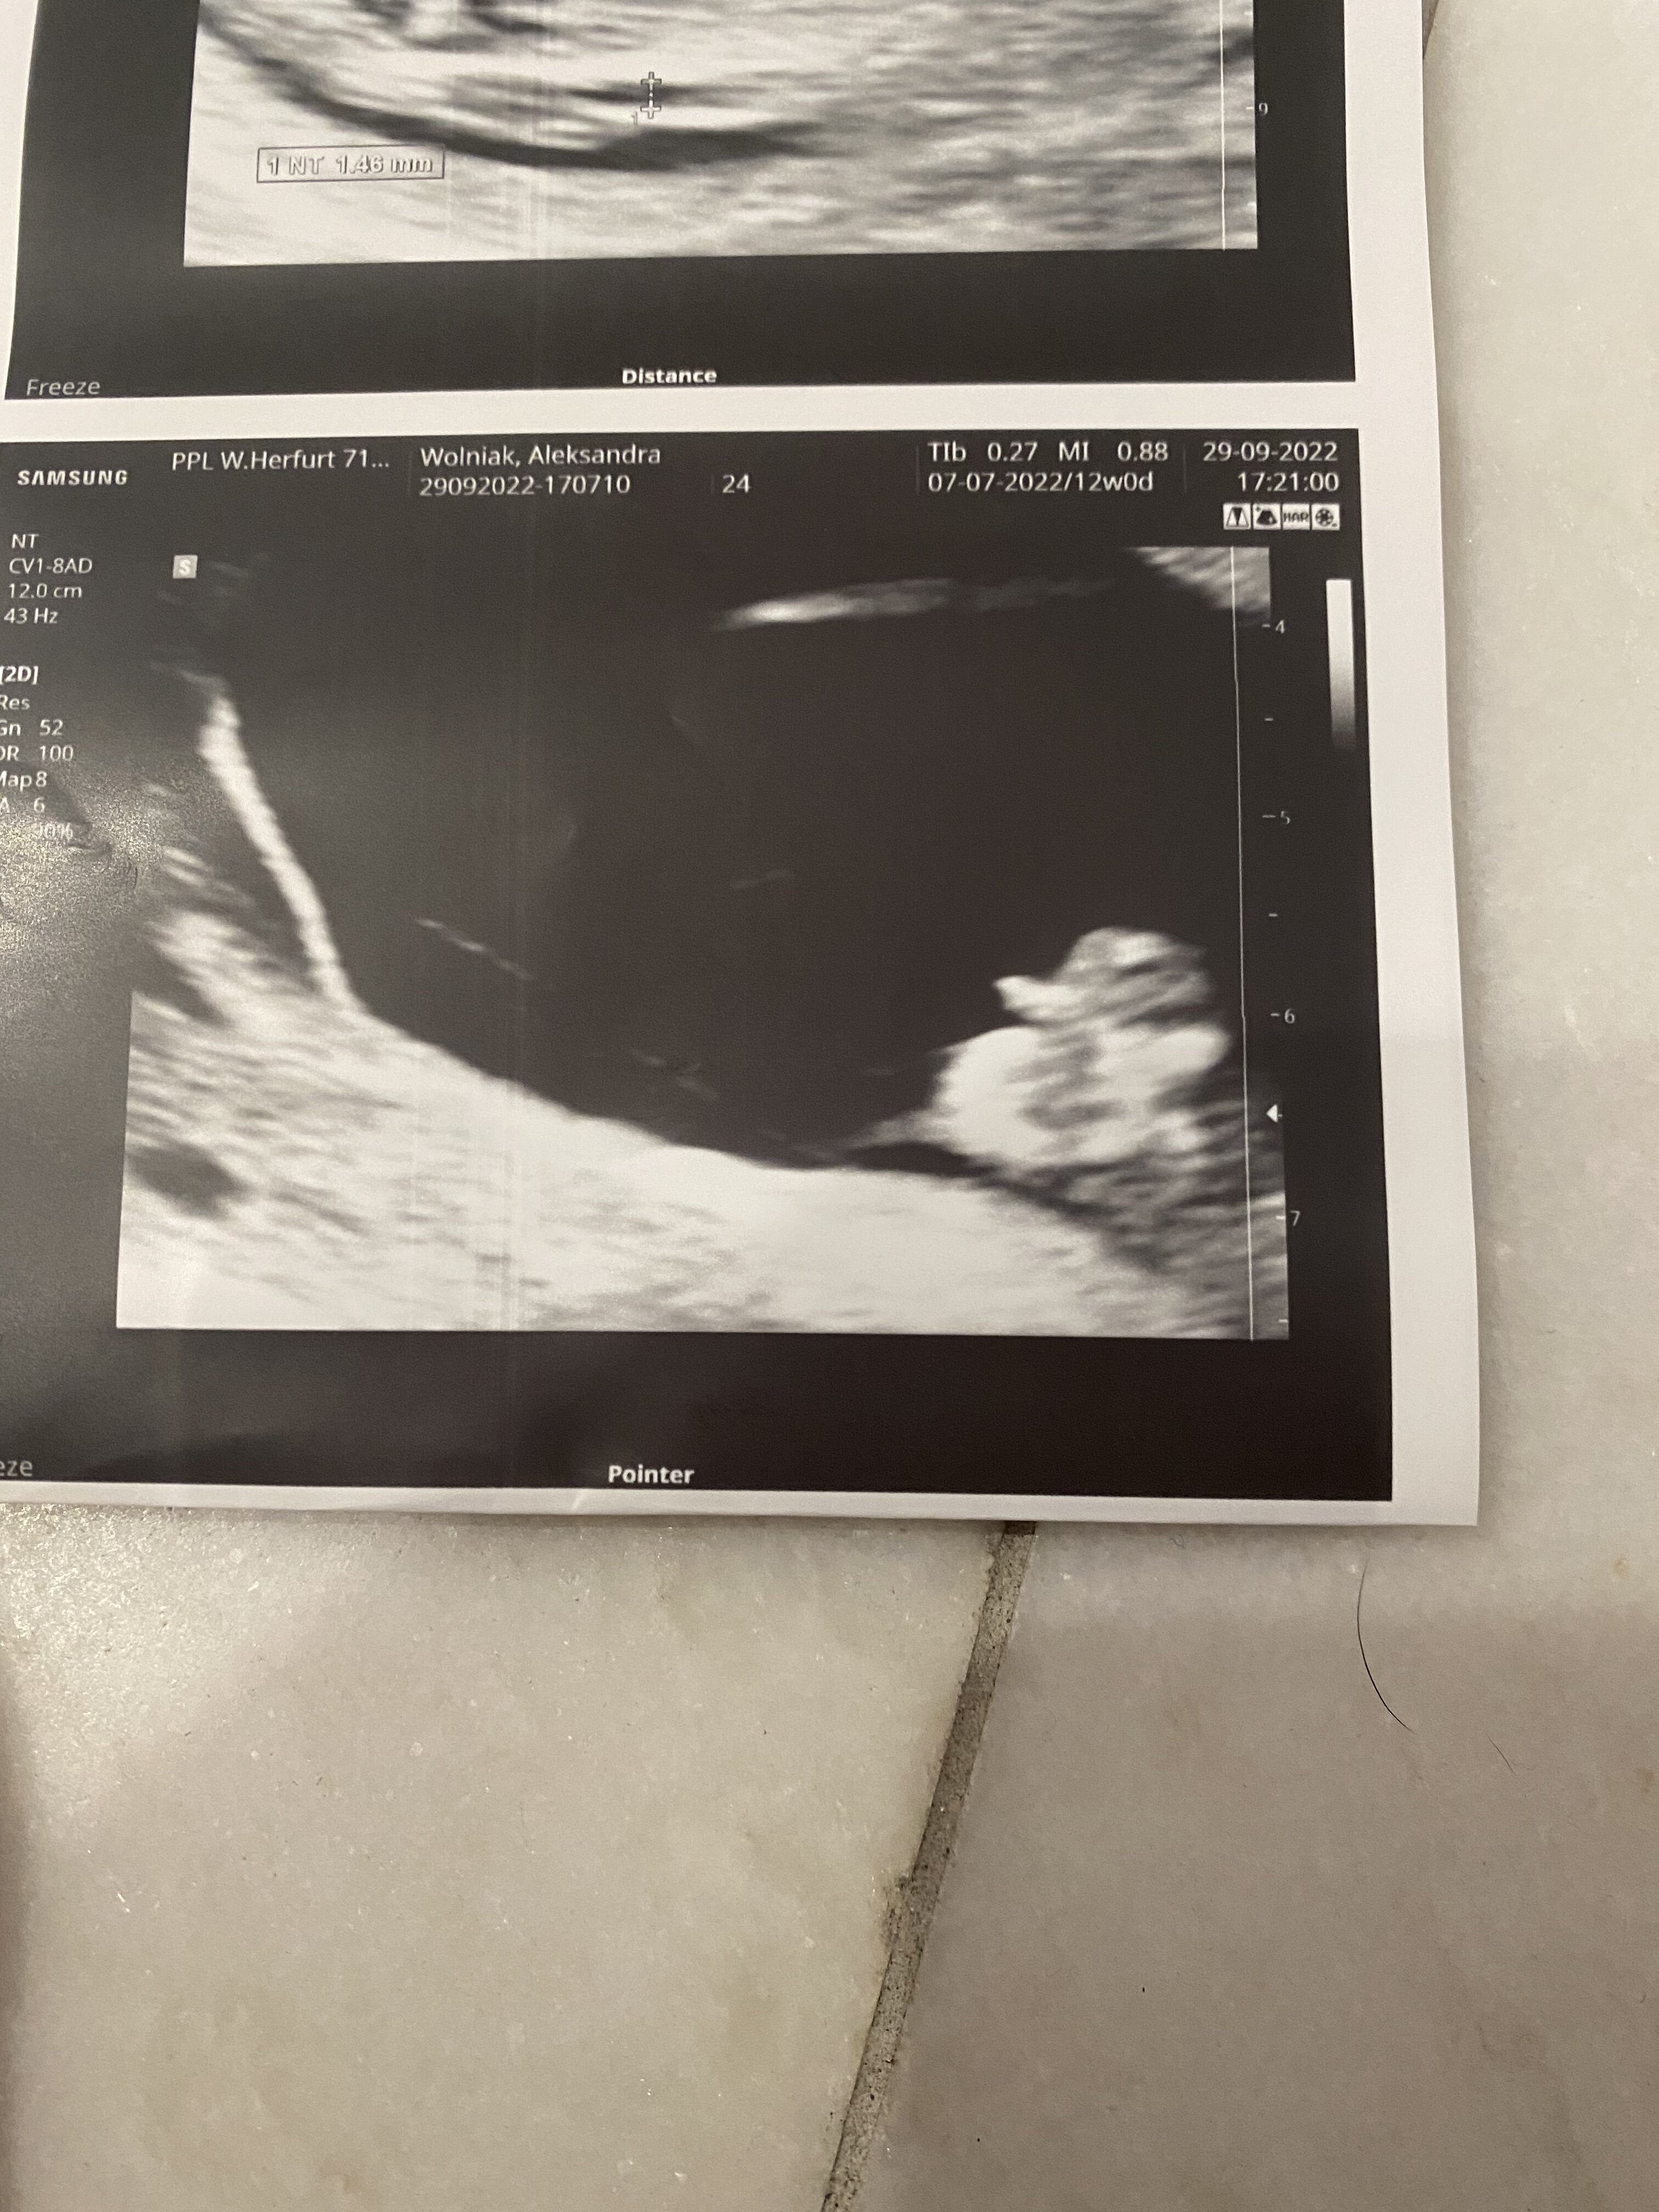

Chłopak czy dziewczynka?

W 13 tygodniu lekarz mówił że raczej chlopczyk